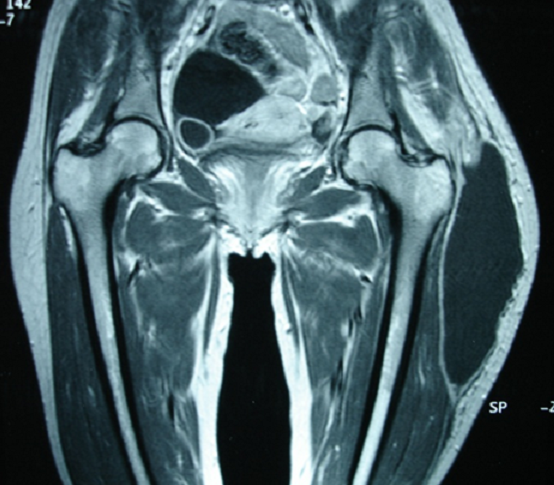

La tuberculose se caractérise par la fréquence et le polymorphisme des localisations extra-pulmonaires qui représentent en moyenne 10 à 20% des cas. L’atteinte musculaire est rare, sa prévalence étant évaluée entre 0,01 et 2 %. Sa survenue sans lésion osseuse sous jacente, comme c’est le cas de notre patiente, est encore plus rare. Il s’agissait d’une patiente âgée de 32 ans sans antécédents pathologiques notables qui était hospitalisée pour une tuméfaction de la cuisse gauche évoluant depuis 4 mois. L’examen avait objectivé une patiente apyrétique, en bon état général. La face supéro-externe de la cuisse gauche était occupée par une masse fluctuante non inflammatoire, non soufflante, indolore de 19 cm de grand axe. L’échographie des parties molles objectivait une collection sous cutanée bien limitée, hypoéchogéne et hétérogène. L’imagerie par résonance magnétique mettait en évidence la présence d’une volumineuse formation kystique de la face externe de la cuisse gauche sans atteinte osseuse sous-jacente. La scintigraphie osseuse était sans anomalie en dehors d’une hyperfixation au niveau du muscle quadriceps gauche. La biologie trouvait un syndrome inflammatoire avec une VS à 140 mm la première heure, une CRP à 88 mg/l et une fibrinémie à 5,4 g/l sans hyperleucocytose. La sérologie VIH était négative. L’intradermo-réaction (IDR) à la tuberculine était à 5 mm. La mise à plat chirurgicale de cette collection avait objectié un liquide purulent dont l’examen bactériologique a permis d’isoler un Bacille de Koch à la culture. Les autres examens complémentaires (radiographies standards, échographie, examens spécialisés, recherche de BK dans les crachats et les urines,…) n’ont pas permis d’objectiver une autre localisation tuberculeuse. En post opératoire, la patiente a été mise sous quadrithérapie anti-tuberculeuse (Rifampicine, Isoniazide, Ethambutol, Pyrazinamide) pendant 2 mois relayée par une bithérapie par Rifampicine et Isoniazide pendant 10 mois. L’évolution était favorable avec un recul de 6 mois.